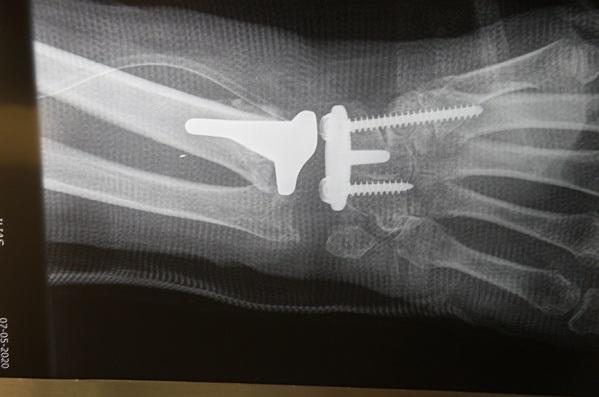

Με ποσοστό επιτυχίας που ξεπερνά το 95% γίνεται πλέον στην Ελλάδα η αρθροπλαστική καρπού, η οποία αποτελεί εξέλιξη αυτής του ισχίου και του γόνατος! «Πράγματι τα αποτελέσματα που μας δίνει η αρθροπλαστική καρπού είναι εκπληκτικά και βοηθά πλέον καθοριστικά στην αποτροπή χιλιάδων αναπηριών, καθώς αποκαθιστά την κατεστραμμένη άρθρωση του χεριού» αναφέρει ο διαπρεπής Χειρουργός Ορθοπεδικός- Μικροχειρουργός Χεριού, Δρ. Ιωάννης Α. Ιγνατιάδης, Διευθυντής Κλινικής Μικροχειρουργικής Άκρων στο Ιατρικό Ψυχικού, που πραγματοποίησε πριν από τέσσερα χρόνια την πρώτη αρθροπλαστική καρπού τύπου «ελεύθερης κίνησης» (freedom) στην Ελλάδα.

Η αρθροπλαστική τύπου “Freedom”επιτρέπει ελεύθερη κίνηση προς όλες τις κατευθύνσεις (πολυκατευθυντική) σε αντίθεση με τις πρώτες που εμφανίσθηκαν και επέτραπαν μόνο κάμψη-έκταση.

Σύμφωνα με τον κ Ιγνατιάδη «η αρθροπλαστική καρπού, και ιδιαίτερα η τύπου “freedom” παρουσιάζει το σοβαρό πλεονέκτημα απέναντι στην αρθροδεσία ότι διατηρείται η κίνηση του καρπού, ενώ στην αρθροδεσία ναι μεν εξαλείφεται ο πόνος και διατηρείτο η ισχύς, πλην όμως καταργούνταν εντελώς η έκταση-κάμψη του καρπού, στη δε εγγύς καρπεκτομή είχαμε μεν κίνηση αλλά υπήρχε σχετική αστάθεια και έλλειψη ισχύος».

Η επέμβαση διαρκεί περίπου δυο ώρες, γίνεται με περιοχική αναισθησία μαζί με ελαφρά ύπνωση. Η διάρκεια νοσηλείας είναι συνήθως δυο διανυκτερεύσεις.

Στο 90% των περιπτώσεων δεν χρειάζεται ιδιαίτερη παραγγελία για το υλικό (custom made), δεδομένου του ότι στο σετ υπάρχουν όλα τα μεγέθη και το υλικό είναι σχεδόν έτοιμο (modular). Σε νέα άτομα η ενσφήνωση γίνεται χωρίς ειδικό τσιμέντο, ενώ σε μεγάλες ηλικίες χρησιμοποιείται κατά την τοποθέτηση ιατρικό τσιμέντο (δίκην πορσελάνης).

Κατά την διάρκεια της αποθεραπείας ο ασθενής πρέπει να ακολουθήσει πιστά τις οδηγίες του γιατρού. Οι ασθενείς που έχουν χειρουργηθεί με αυτή τη μέθοδο απέκτησαν μεγάλο εύρος κίνησης (range of motion) και επανήλθαν απόλυτα ικανοποιημένοι έχοντας ένα πλήρες followup για 5 χρόνια χωρίς άλλα προβλήματα.